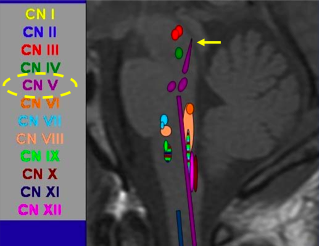

What cranial nerves are associated with the medulla, pons and midbrain?

*